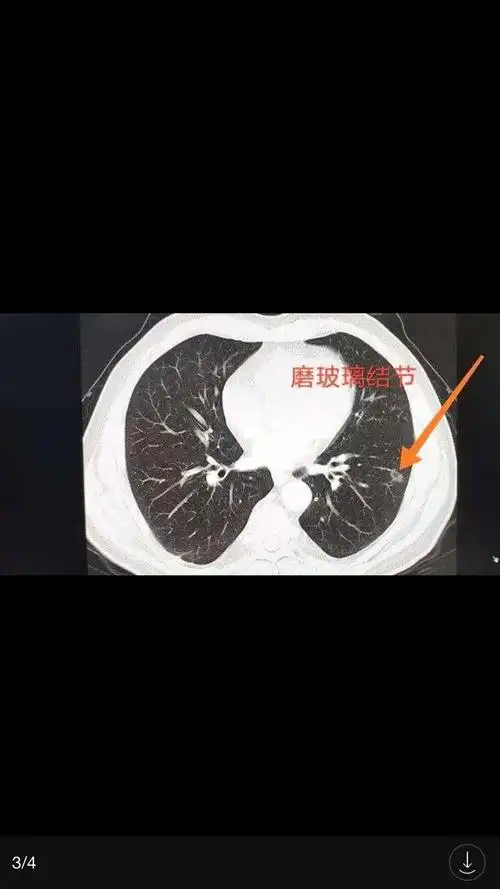

肺结节良恶性的六大鉴别要点